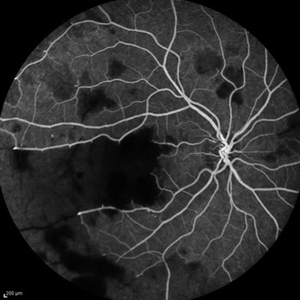

Idiopathic Occlusive Retinal Vasculitis (Late Stage) Idiopathic Occlusive Retinal Vasculitis (Late Stage)May 31 2014 by Hamid Ahmadieh, MD Wide-field FA image of the left eye of a 28-year-old woman with idiopathic occlusive retinal vasculitis 6 months after the onset. Photographer: Elham Salehi, Negah Eye Center, Tehran Imaging device: Heidelberg Spectralis Condition/keywords: capillary closure, macular infarction